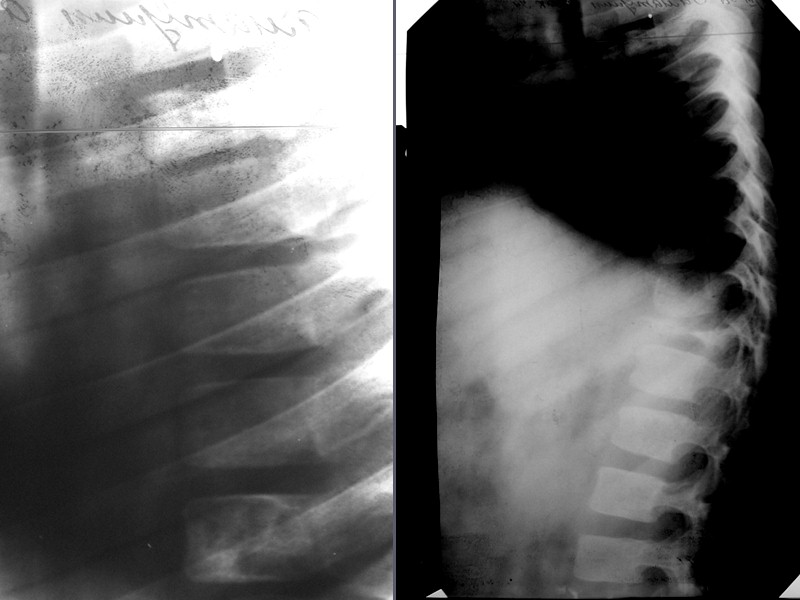

Хондрома До 10-15% от всех доброкачественных костных опухолей Выявляется чаще в возрасте от 10 до 40 лет Чаще множественные поражения (двусторонние, не симметричные) Малигнизируется в хондросаркому (чаще при локализации в ребрах, длинных трубчатых костях, костях таза) Поражаются преимущественно короткие трубчатые кости (фаланги), ребра, грудина, Редко - позвонки, кости таза, длинные трубчатые кости Солитарные поражения длинных трубчатых костей – дифференцируем с кистой, фибромой, метастазом

По расположению в кости выделяют: Экхондрома (переферически) Проявляется либо краевой деструкцией, на уровне которой располагается добавочное образование с широким диапазоном всевозможных обызвествлений. Энхондрома (центрально) Выглядит как очаг вздутия, негомогенной структуры (хрящевой фон с вкраплениями костного вещества), окруженный замыкательной пластинкой – «скорлупой» За счет вздутия и истончения кортикального слоя часто осложняется патологическим переломом